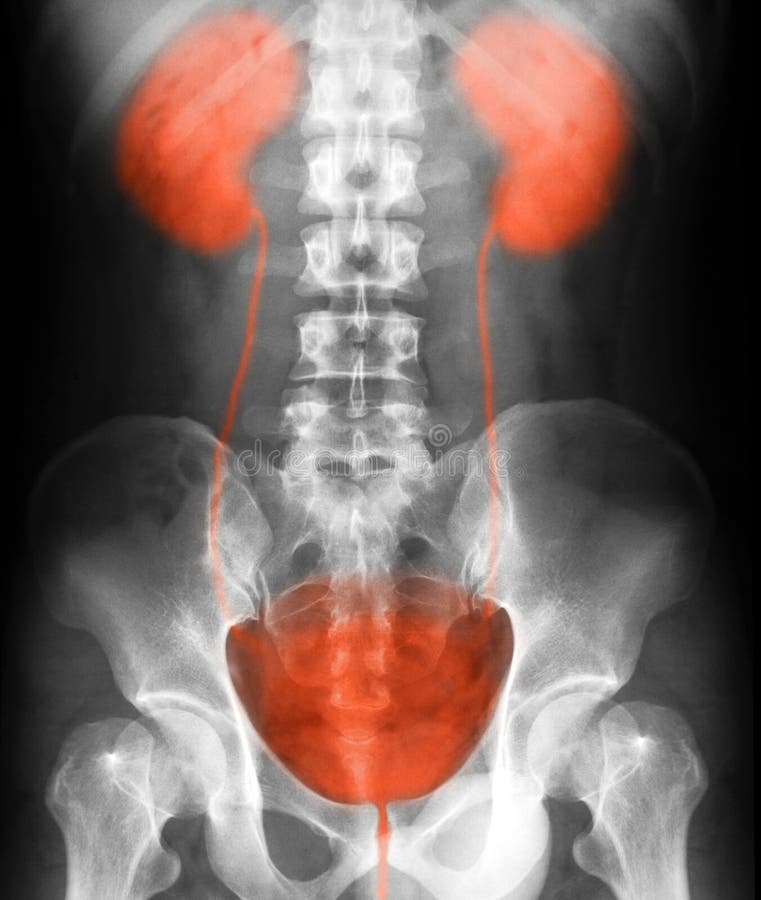

Медицинские изображения: Обзорная рентгенография урография

Раздел: Фокус на знании